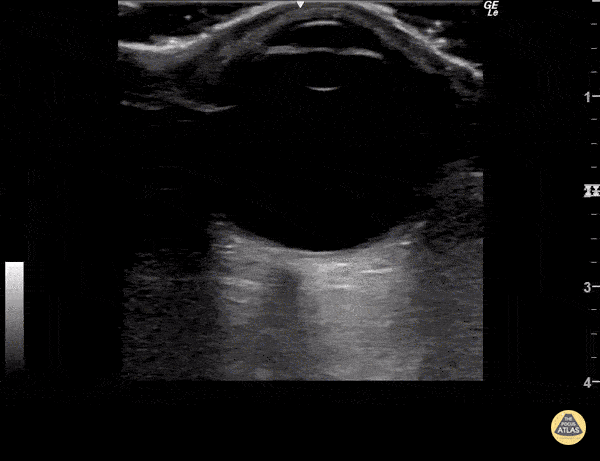

Orbital - Looking Around - Normal Exam

Normal ocular ultrasound over closed eyelid as patient moves eye medially and laterally. Sukh Singh, MD